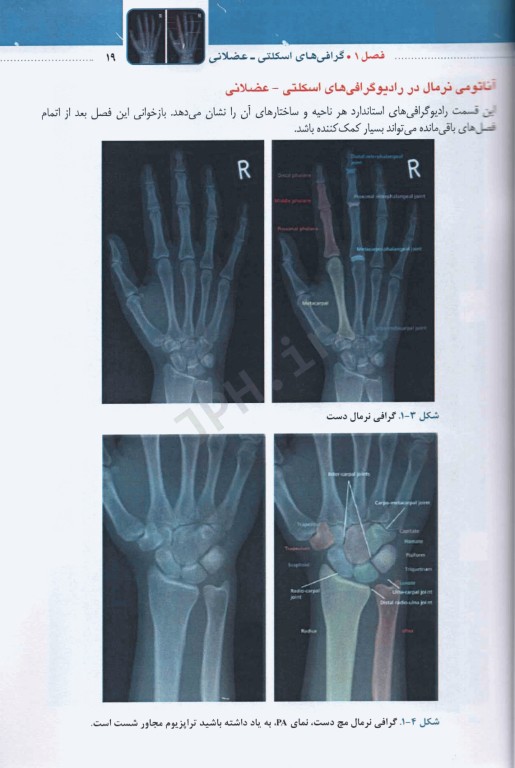

کتاب تفسیر آسان گرافی‌های اسکلتی عضلانی تالیف اندروکی براون و دیوید جی کینگ ترجمه دکتر مهراد عقیلی توسط انتشارات تیمورزاده به چاپ رسیده است. امروزه روش‌های نوین و گوناگونی برای تشخیص آسیب‌های اسکلتی- عضلانی وجود دارد ولی در دسترس‌ترین ارزان‌ترین آنها گرافی ساده است که نقش مهمی در سیر درمان بیماران دارد. تفسیر گرافی‌های اسکلتی- عضلانی برای همه گروه‌های کادر درمان ضرورری است.